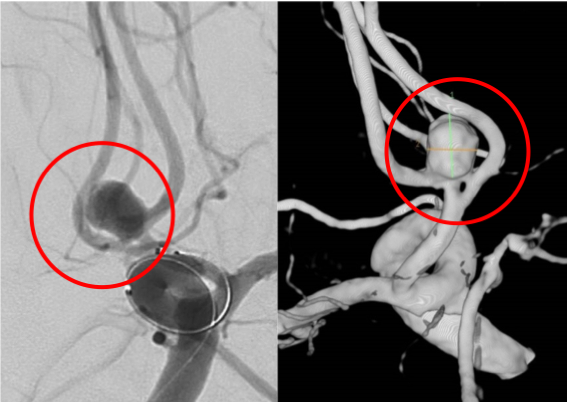

内頚動脈瘤

術前の造影写真です。〇内に脳動脈瘤が造影されています。

術後の造影写真です。主幹動脈は温存できており、動脈瘤は造影されなくなっています。